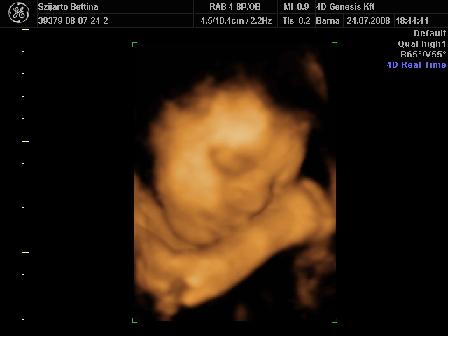

Bettyna: Gratulálok a kis kukacoshoz!!! :wink: :lol: Nagyon jók ezek a 4D-s képek róla!!! Annyira jól lehet látni a kis arcát!! Szuper!!